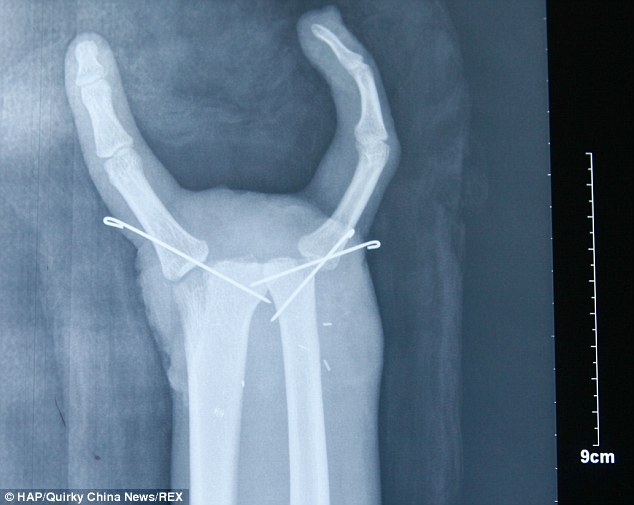

A gép szilánkosra törte a két csuklóját és az ujjcsontjait is. Kollégái azonnal rohantak vele a kórházba, de a röntgen alapján nem sok remény maradt a keze megmentésére. Ekkor döntöttek úgy az orvosok, hogy mindent megtesznek, hogy megmentsék.

A jobb kezére a hüvelykujjával szemközt a bal kisujját varrták rá, a bal kezén pedig eltávolították a középső ujját, így a mutató- és gyűrűsujj megmaradt – így alakult ki a másik harapófogó.

A műtét 9 órán keresztül tartott, és sikeresnek mondható, hiszen a férfi azóta már az ujjait is be tudja hajlítani.